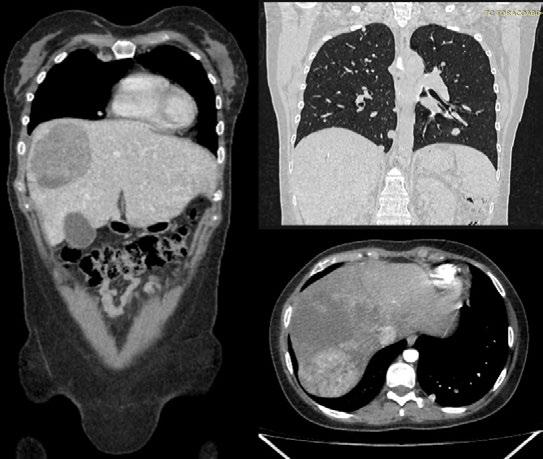

I hope these insights inspire curiosity, collaboration, and compassion, reminding us why we do this work. I hope to see you in Chicago, Illinois, for ASCO 2026.

Chair, ASCO 2025 Annual Meeting Scientific Program Committee; Director, Breast Cancer Research, Sarah Cannon Research Institute, Nashville, Tennessee, USA